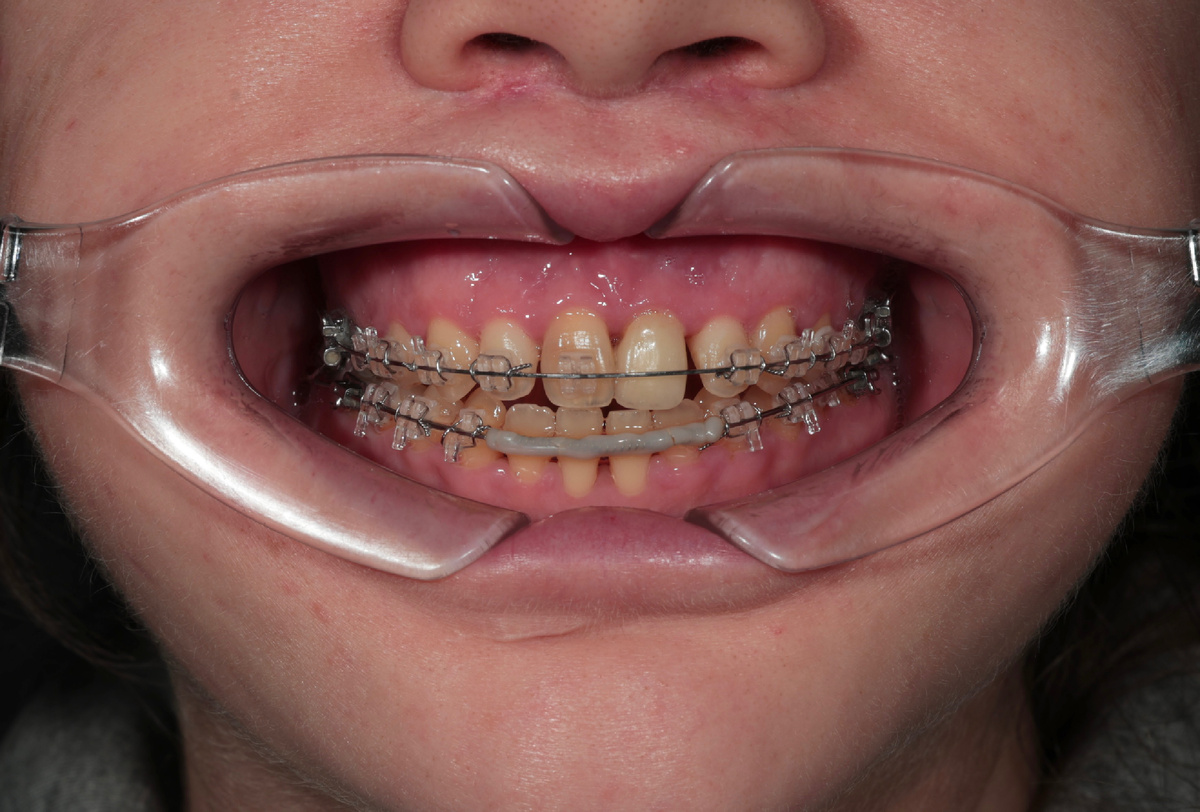

Весной 2025 она написала снова: - "Здравствуйте, я всё-таки надумала лечиться у вас". Пришла - всё с тем же расширителем на верхней челюсти, с остатками брекетов.

Состояние зубов на момент обращения

Мы провели полную диагностику. Ситуация непростая - кортикальная кость в значительной степени утрачена, часть нижних резцов подвижна, прикус не смыкается как нужно. Скелетный третий класс - нижняя челюсть выдвинута вперёд, плюс последствия многолетнего лечения, которое не было доведено до конца.

На фронтальных зубах нижней челюсти брекеты вообще не ставились - судя по всему, предыдущий специалист понимал, что ситуация нестабильна и не рисковал. Это само по себе говорит о многом.

Сняли брекет-систему: